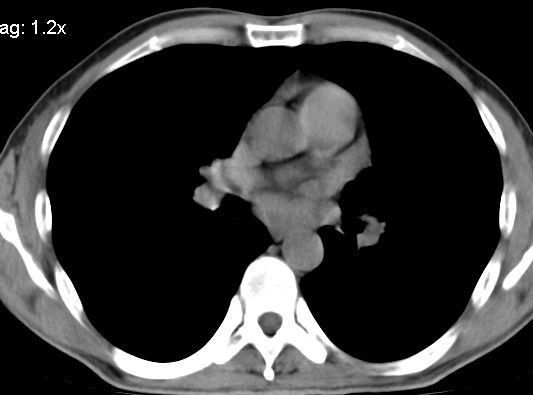

标题: CT10147:男、55岁,咯血10天,有结核病史。 [打印本页]

标题: CT10147:男、55岁,咯血10天,有结核病史。

左上肺见软组织密度肿块影,边缘呈分叶状,可见毛刺,肺门纵隔淋巴结增大,考虑左侧周围型肺癌。左上肺陈旧性结核纤并维化。

左肺分叶状肿块,有毛刺,肺门淋巴结增大.支持左周围型肺癌,肺门淋巴结转移,陈旧性肺结核.

左上肺尖后段上面陈旧性结核,下面邻近左肺门旁可见软组织肿块影,与上肺v关系密切,左肺门及气管隆突下可见增大的淋巴结影,考虑1.左上肺ca(周围型)伴肺门纵隔内淋巴转移 2.左上肺陈旧性tb